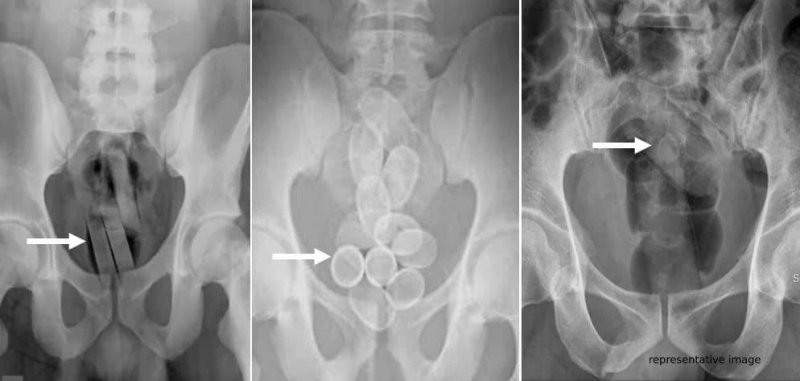

“There was something wrong with him, we felt he was hiding something,” one of the customs officials who arrested him told prosecutors. “We found him hiding a condom in his rectum,” he added. The suspect admitted to consuming drugs and confessed to having homosexual feelings, besides being HIV positive.